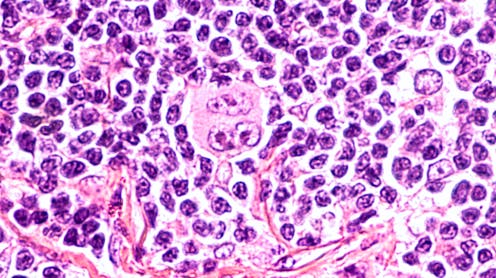

Se acaba de publicar en el British Journal of Haemathology el siguiente caso clínico: Varón de 61 años con inflamación de los ganglios y pérdida de peso, recibía hemodiálisis por insuficiencia renal terminal después de un trasplante renal fallido. Se le diagnostica un linfoma de Hodgkin clásico en estadio III (el linfoma afecta a áreas ganglionares localizadas a ambos lados del diafragma o por encima del diafragma y en el bazo).

Según los autores, la hipótesis es que la infección por SARS-CoV-2 desencadenó una respuesta inmunitaria antitumoral: las citocinas inflamatorias producidas en respuesta a la infección podrían haber activando células T específicas con antígenos tumorales y células asesinas naturales contra el tumor. El SARS-CoV-2 le había curado el linfoma.